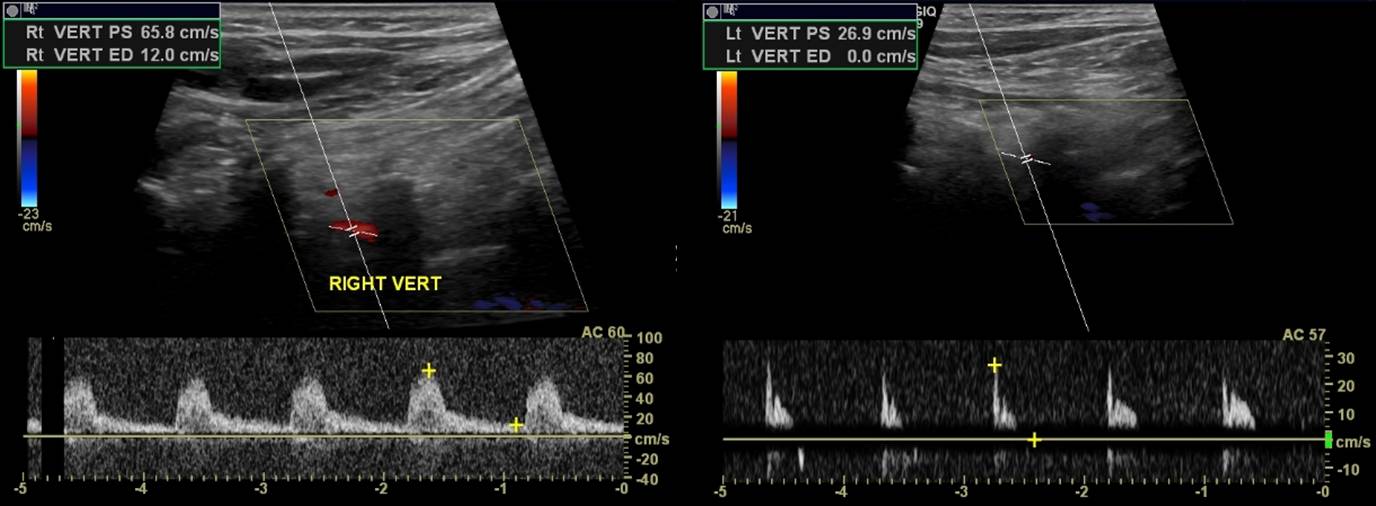

Prior to subclavian steal there is a pattern of flow with a prominent dicrotic notch. This is dubbed “bunny rabbit pattern”. It is the stage before to and fro flow:

Sometimes, bi-derectional flow may precede retrograde flow:

Vertebral artery to and fro duplex. A precursor of subclavian steal syndrome

Vertebral artery “to and fro” on ultrasound